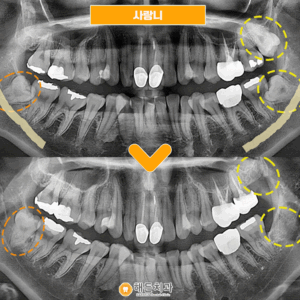

사랑니발치 환자분의 간식선물🍩

안녕하세요~ 해든치과입니다! 오늘은 사랑니 발치하신 환자분께서 사랑니 때문에 걱정이 많았는데 안아프게 잘 뽑아주셔서 감사하시다며 간식선물을 해주셨습니다ㅎㅎ     잇몸뼈 안쪽으로 매복되어 있던 사랑니라 집 근처 치과에서 큰 치과에 가야한다고 들으시고 해든치과에 내원해주셨습니다     다행히 사진촬영해보니 발치가 가능한 정도이셔서 해든치과에서 사랑니를 발치하셨습니다🤗   큰병원에 가라니 막막하고 무서운 더보기…